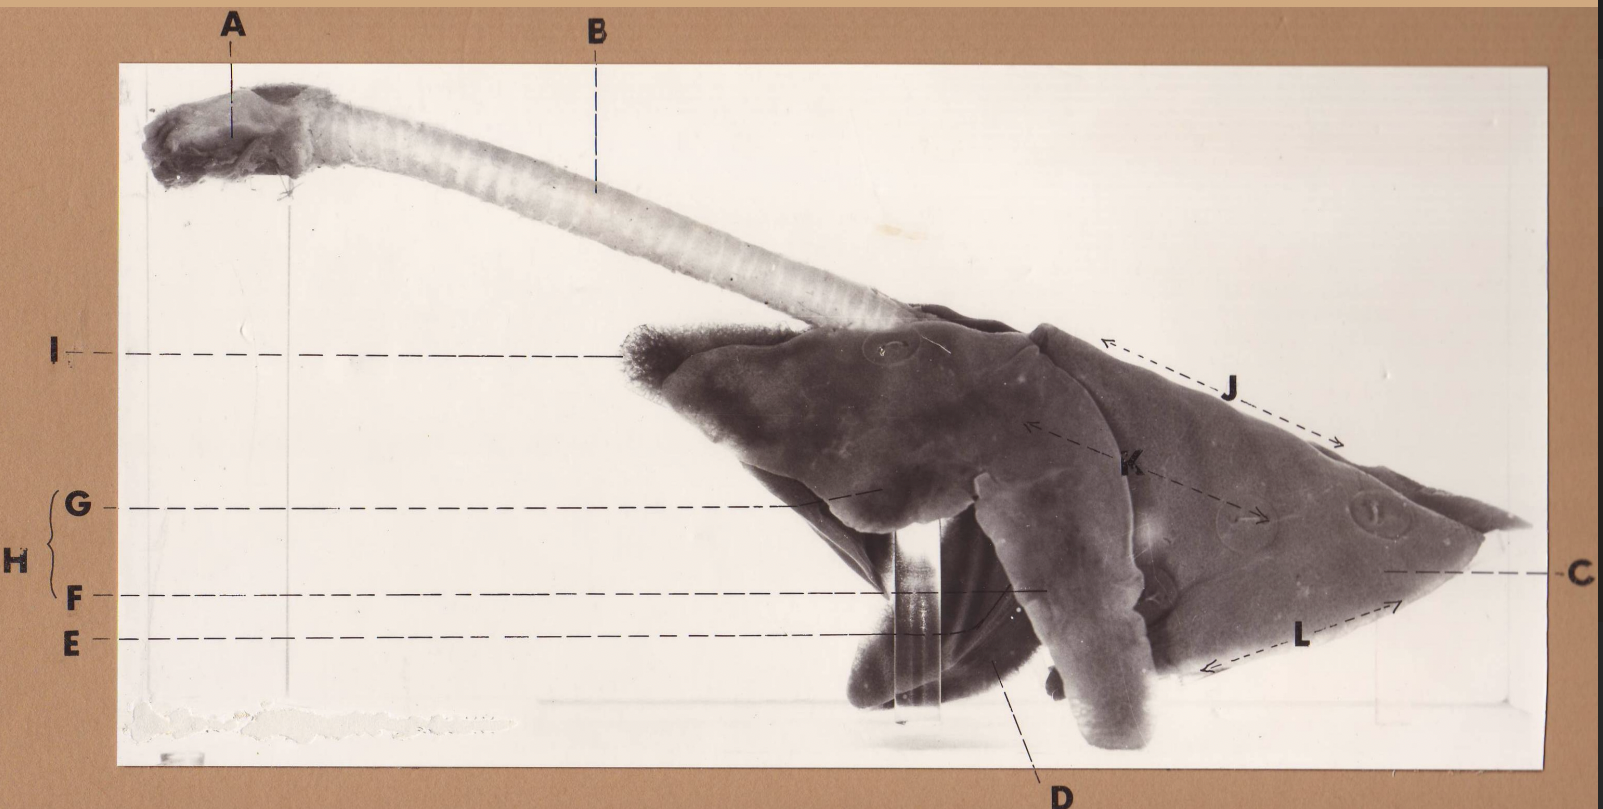

A

(cat larynx/trachea/lungs, L lateral)

larynx

B

(cat larynx/trachea/lungs, L lateral)

trachea

C

(cat larynx/trachea/lungs, L lateral)

caudal lobe

D

(cat larynx/trachea/lungs, L lateral)

middle lobe

E

(cat larynx/trachea/lungs, L lateral)

cardiac notch

F

(cat larynx/trachea/lungs, L lateral)

caudal segment, cranial lobe

G

(cat larynx/trachea/lungs, L lateral)

cranial segment, cranial lobe

H

(cat larynx/trachea/lungs, L lateral)

cranial lobe

I

(cat larynx/trachea/lungs, L lateral)

apex

J

(cat larynx/trachea/lungs, L lateral)

dorsal border

K

(cat larynx/trachea/lungs, L lateral)

costal surface

L

(cat larynx/trachea/lungs, L lateral)

basal border